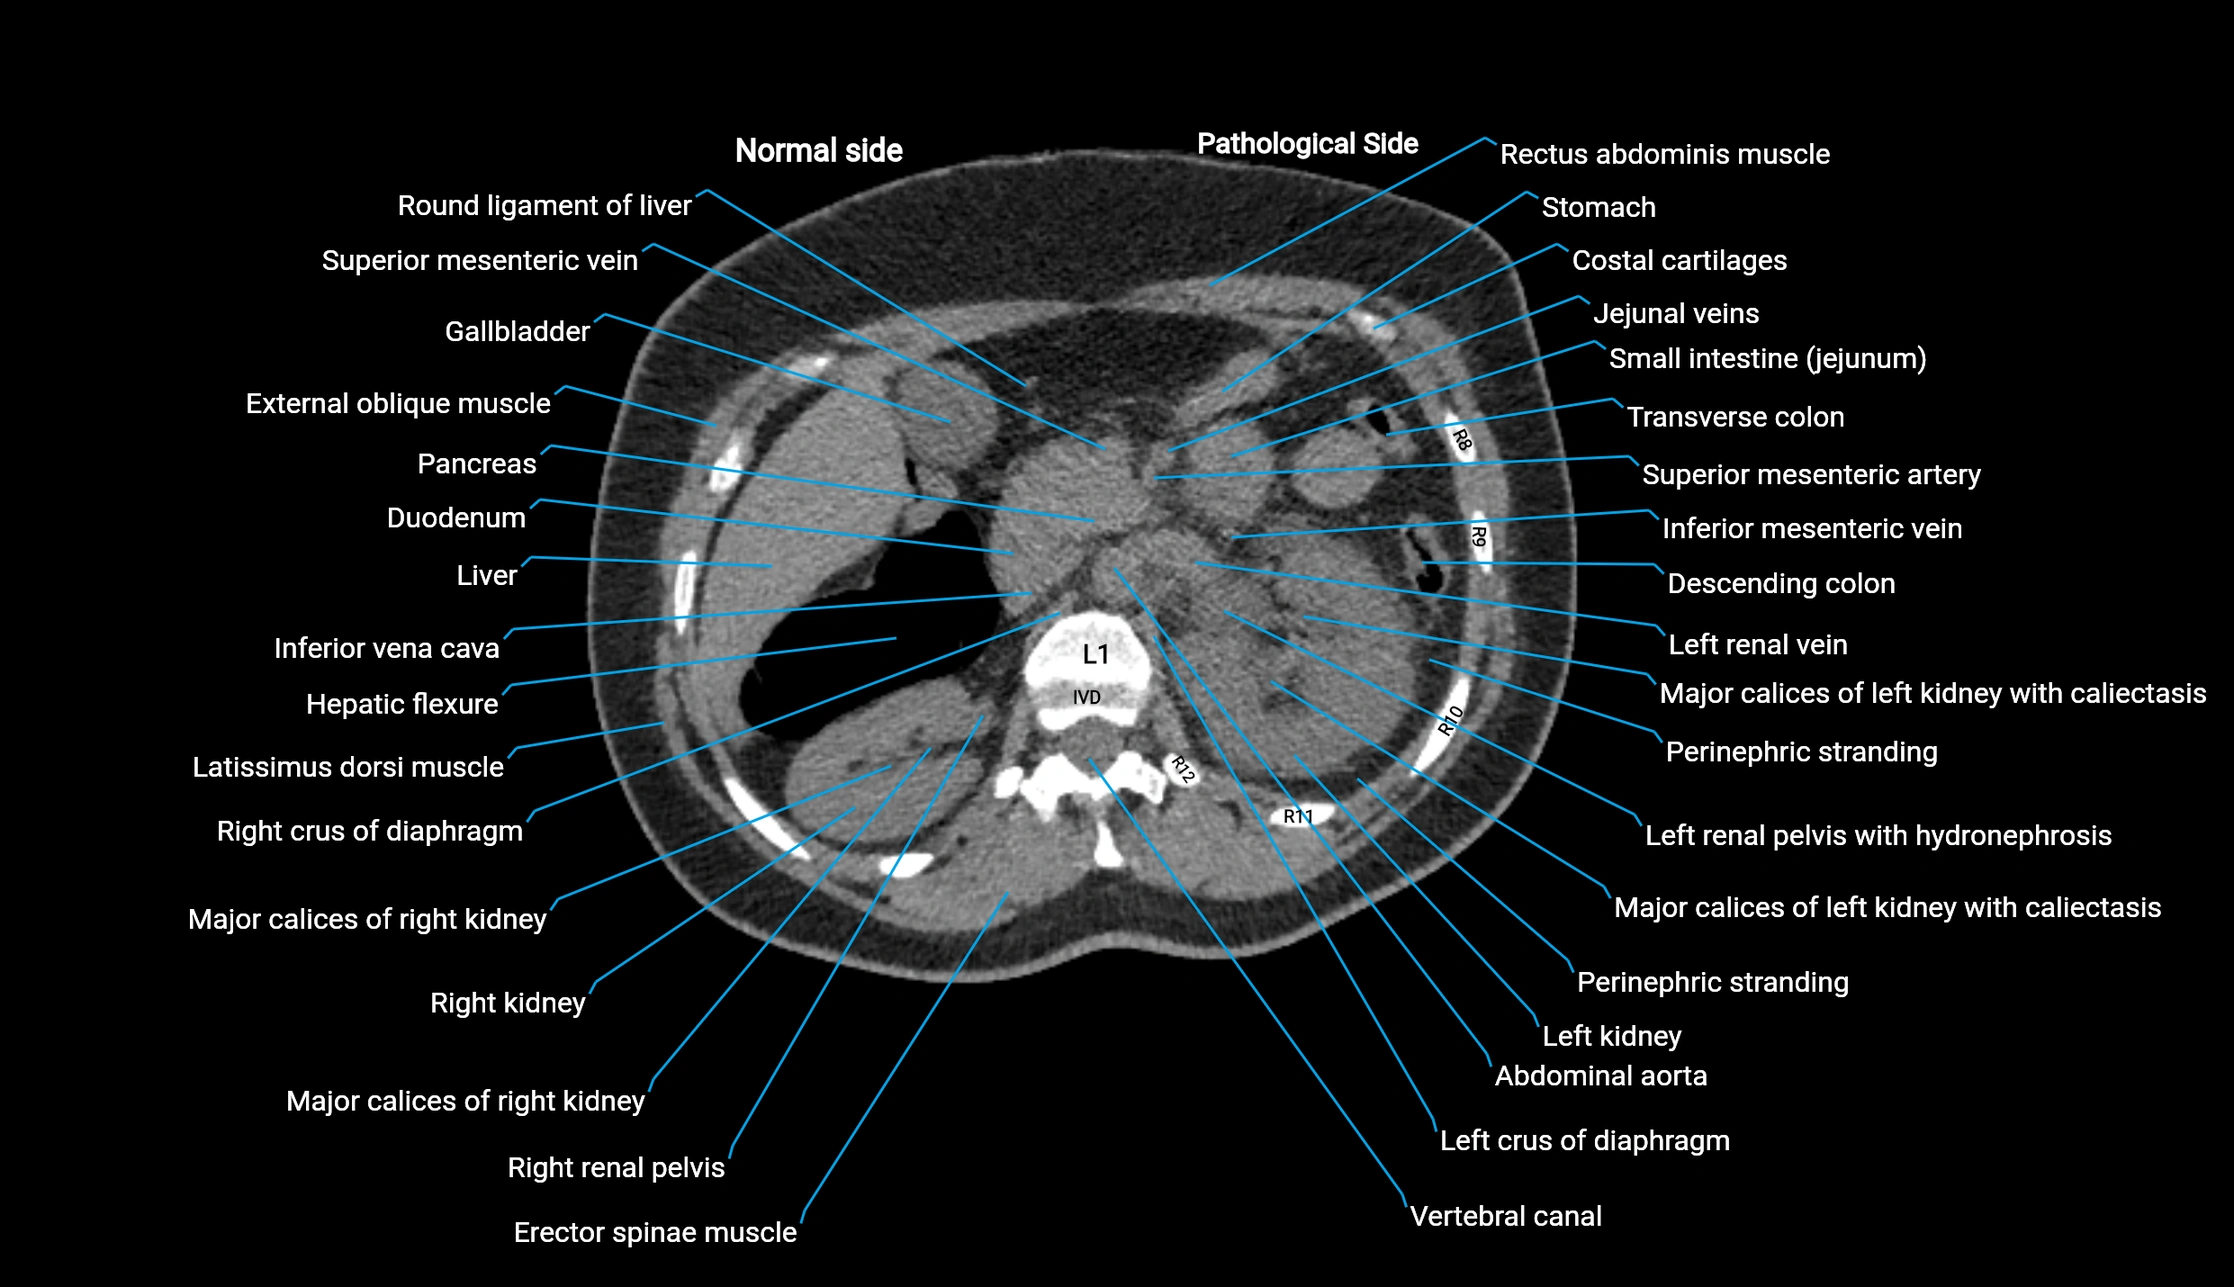

CT image

image